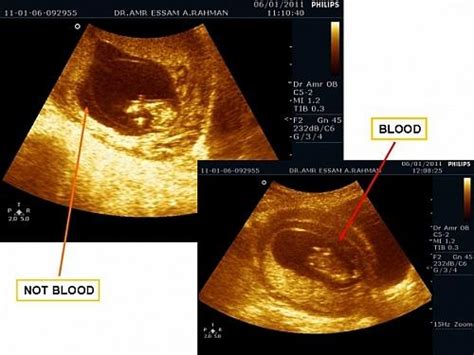

先兆流产是指在怀孕早期出现的阴道少量出血,时下时止,伴有轻微下腹痛和腰酸的一种症状,它很可能导致流产,也有可能经过适当治疗后继续妊娠。

这个是先兆流产的症状,你一定要好好休息,心情要放轻松一点,先观察看看,如果分泌物增多或颜色是红的,或腰胀腰痛,腹痛或胀的话就要去医院了。